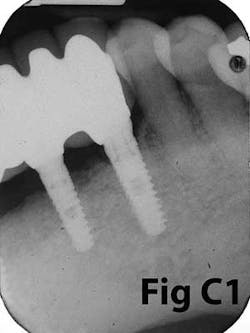

Fig. 7: Failing implants for mandibular overdenture were placed in atrophic mandible with inadequate attached tissue.Comparison